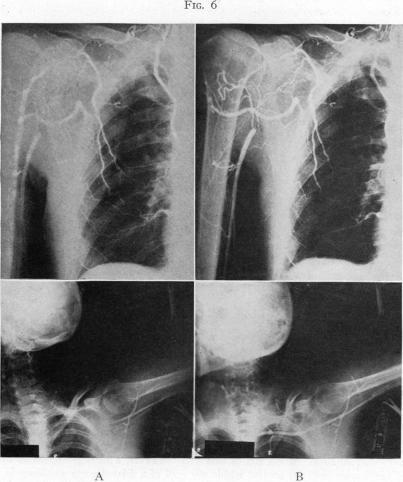

The Valsalva Maneuver: An Aid for the Contrast Visualization of the Aorta and Great Vessels.

Ann Surg. 1949 Sep;130(3):398-414.